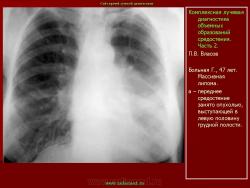

Средостение.  "Опухолевый рост".